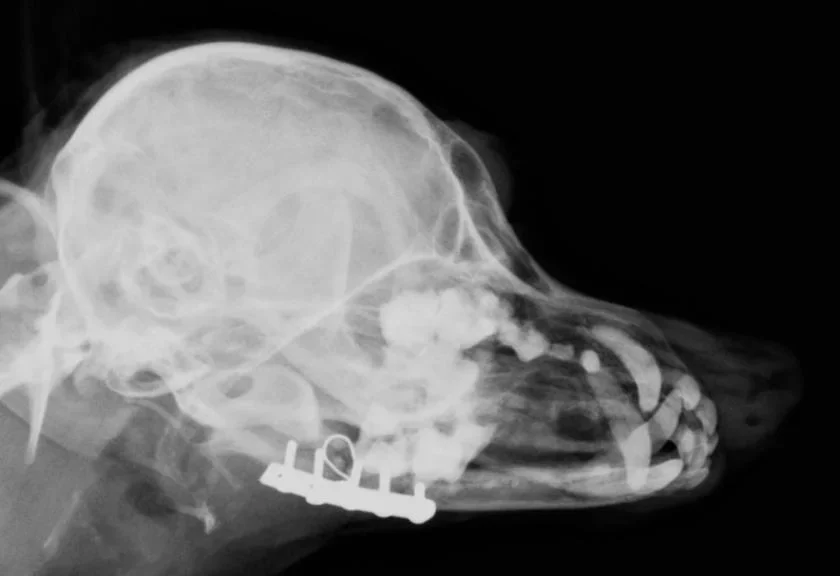

Galería de casos clínicos

Casos clínicos de cirugía (tejidos blandos, traumatología, neurocirugía, artroscopia)